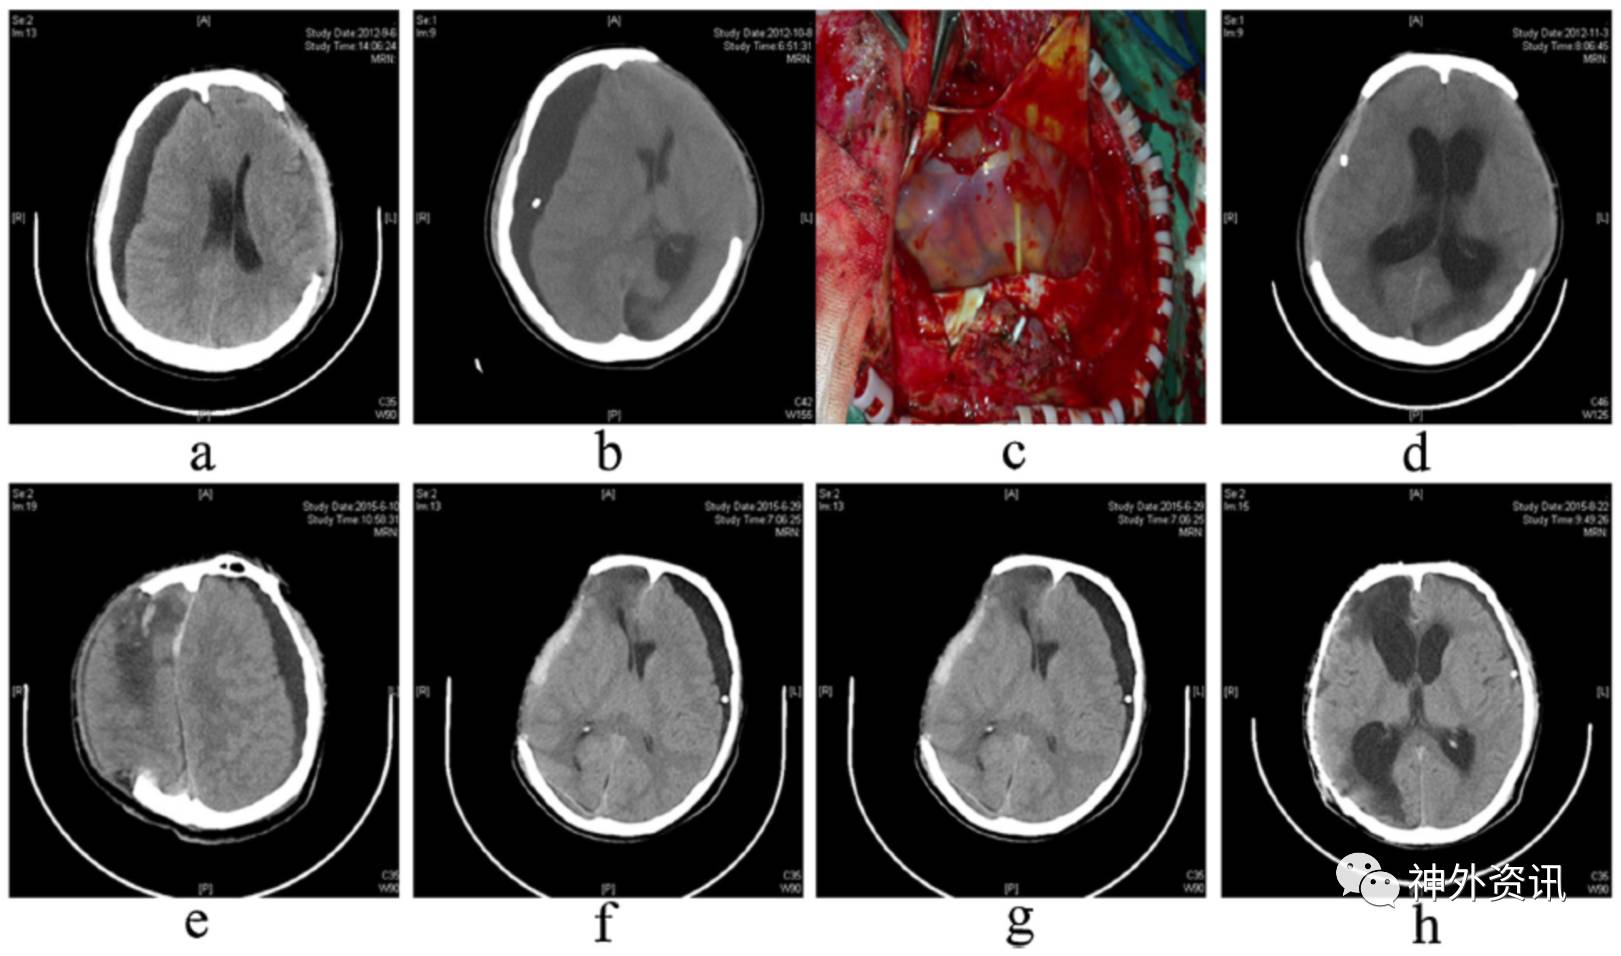

图1. a-d.硬膜下积液侧作去骨瓣颞肌贴敷术治疗难治性硬膜下积液;e-h.最初颅骨缺损处修补术治疗难治性硬膜下积液。

2012年至2015年间,13例重度颅脑外伤患者在去骨瓣减压后出现对侧硬膜下积液。其中,男性7例,女性6例;平均年龄为32.1岁。11例为车祸致伤和2例高处坠落伤。术后1周开始出现对侧硬膜下积液,并进行性加重。经加压包扎、头低位、钻孔引流或Ommaya囊植入引流等治疗,硬膜下积液反复发生。作者将13例患者分为两组,6例行硬膜下积液侧去骨瓣颞肌贴敷术(贴敷组);7例患者行最初颅骨缺损处修补术(颅骨修补组)。两组患者在心率、体温、呼吸、血压和术前GCS评分等指标上未见显著性差异(图1、表1)。